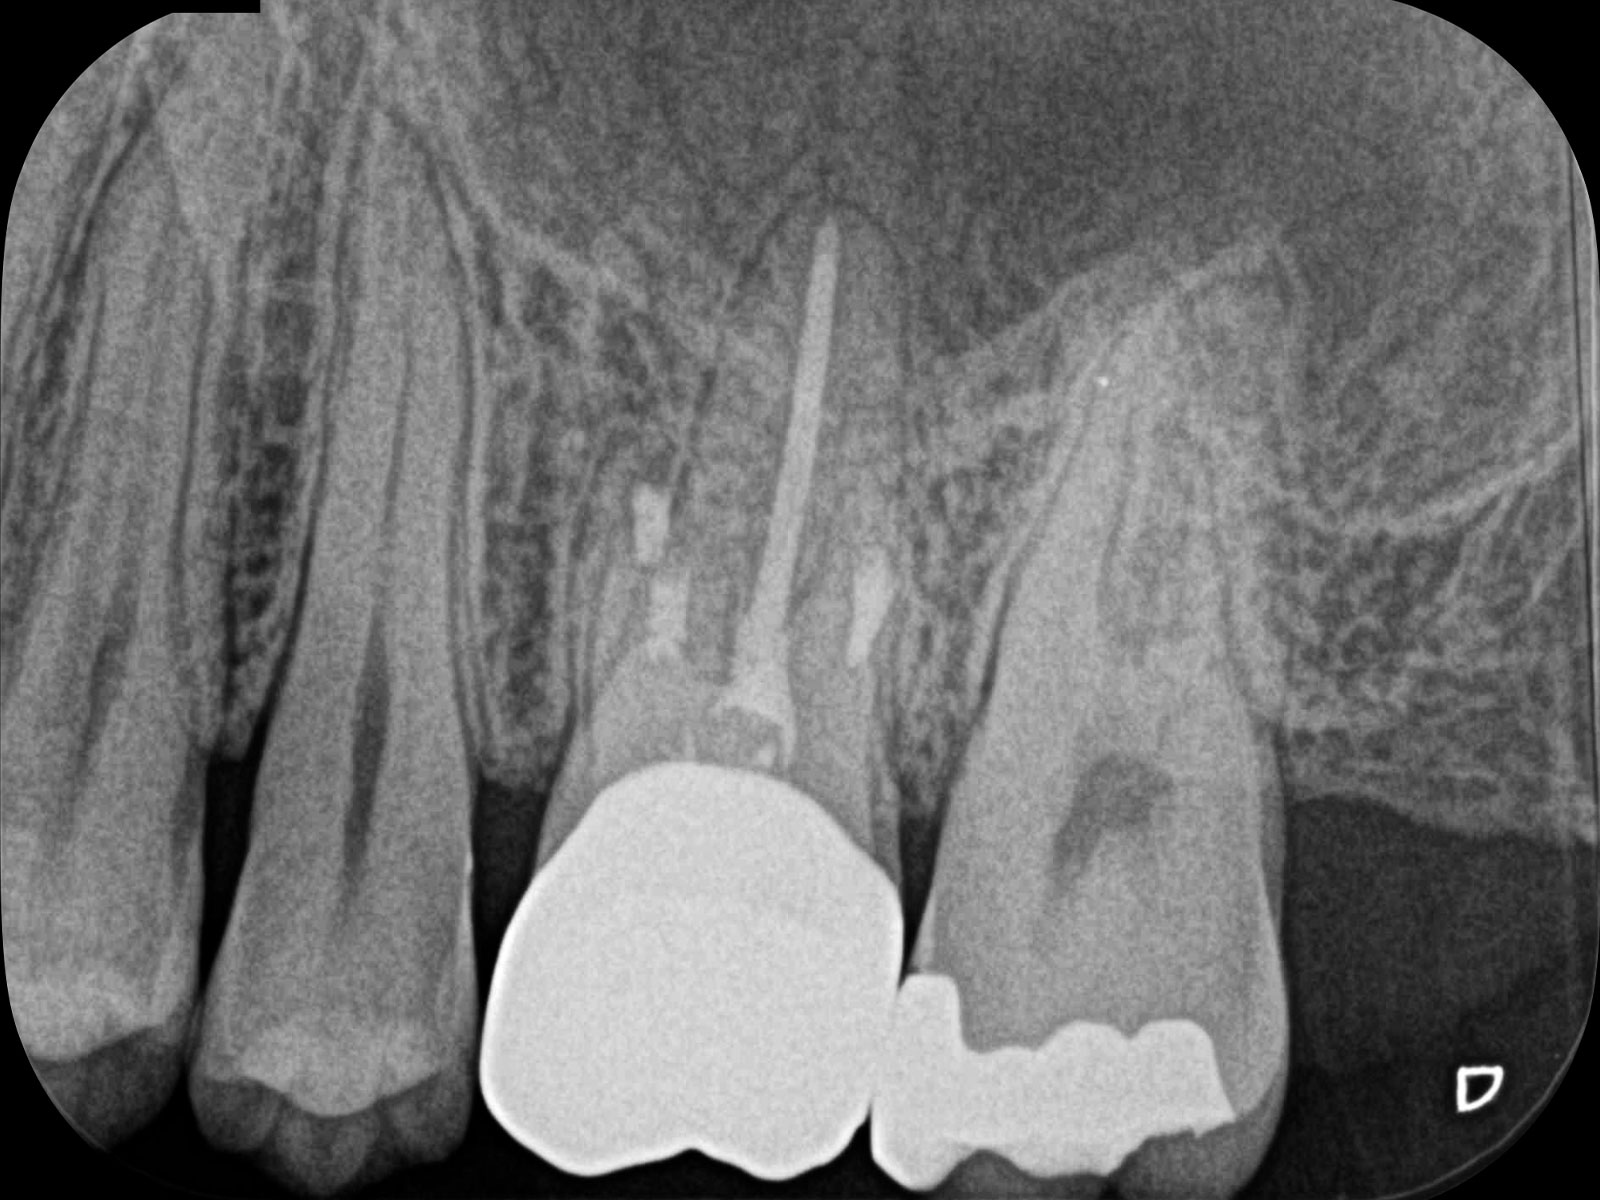

丸の部分が病巣です。CT画像によって、左の画像(Before)では黒く映っている病巣が右の画像(After)ではなくなっていることが確認できます。レントゲン画像ですと、ここまでクリアに写りませんので、病巣を見落としてしまう可能性があります。